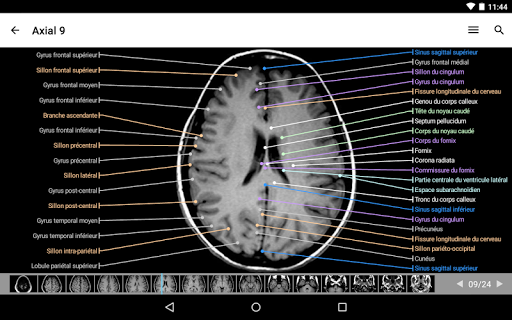

IMAIOS e-Anatomy adalah atlas anatomi manusia untuk dokter, ahli radiologi, mahasiswa kedokteran, dan teknisi radiologi. Dapatkan cuplikan lebih dari 26.000 gambar medis dan anatomi secara gratis sebelum berlangganan atlas anatomi manusia terperinci kami.

e-Anatomy memiliki lebih dari 26.000 gambar yang berisi serangkaian gambar dalam tampilan aksial, koronal, dan sagital serta radiografi, angiografi, gambar diseksi, bagan anatomi, dan ilustrasi. Semua gambar medis diberi label dengan cermat, lebih dari 967.000 label tersedia dalam 12 bahasa termasuk Terminologia Anatomica Latin.

- Gulir set gambar dengan menyeret jari Anda

- Perbesar dan perkecil

- Ketuk label untuk menampilkan struktur anatomi